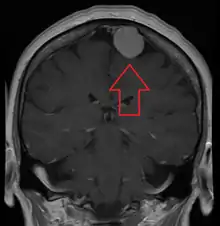

Meningiomas are visualized readily with contrast CT, MRI with gadolinium,[17] and arteriography, all attributed to the fact that meningiomas are extra-axial and vascularized. CSF protein levels are usually found to be elevated when lumbar puncture is used to obtain spinal fluid.

| A contrast-enhanced CT scan of the brain, demonstrating the appearance of a meningioma | |